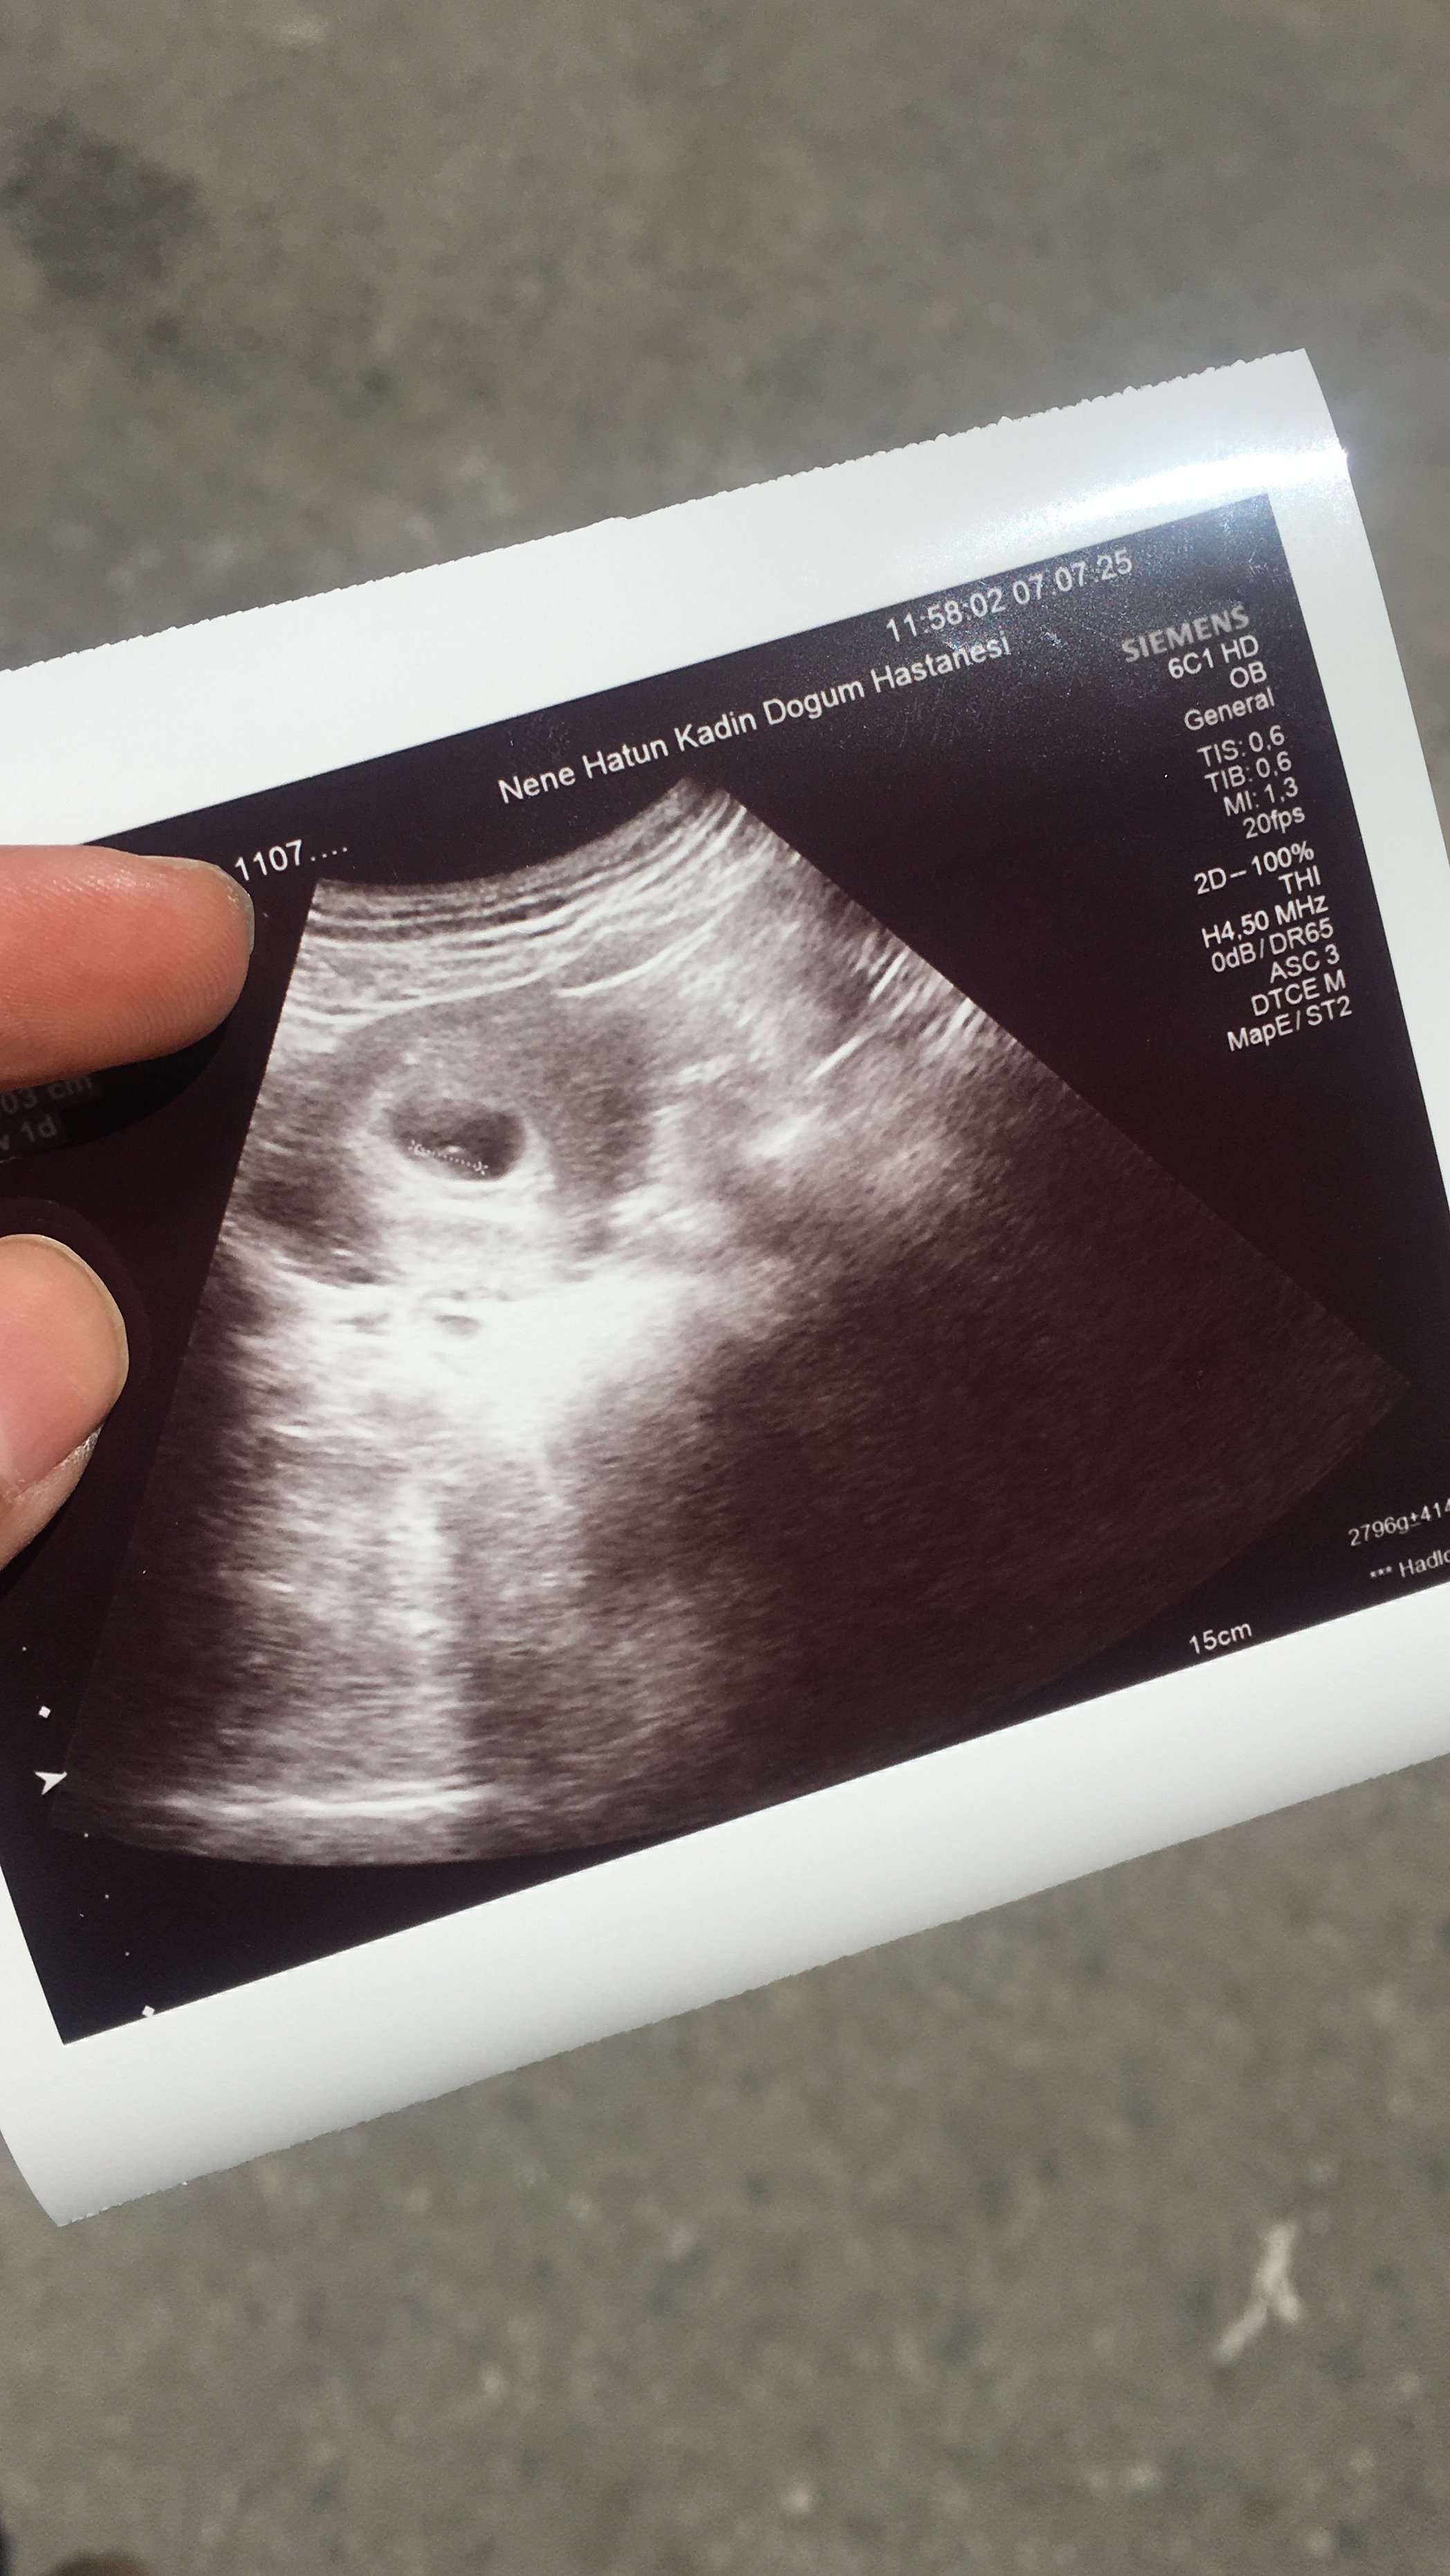

10 hafta 6 günlük bebişim 3 oğlum var tabiki önceliğim sağlıklı olması anlayan varmı çok merak ettım doktor soylemedı şimdiden tşk ederim cevap veren olursa 🥰🥰